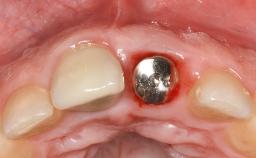

A 70-year-old female patient was referred by her general dentist to the periodontist for assessment and management of an infection associated with implant 36. The general dentist had noted suppuration on probing during examination.